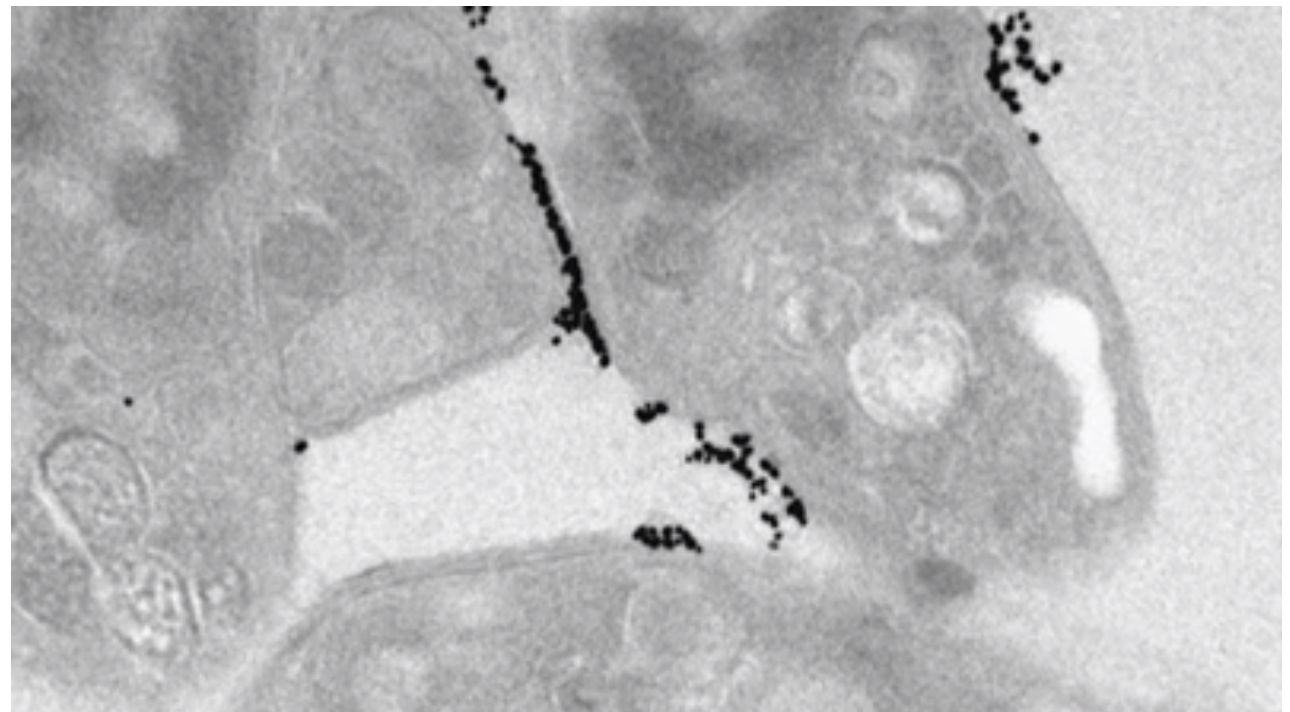

Gold Nanoparticles – Strange properties and applications

Gold nanoparticles exhibit extraordinary properties quite unlike those of the bulk metal. These properties can be exploited in a variety of assay applications, including lateral flow tests, microscopy, flow cytometry and FRET assays. There are also a number of therapeutic applications, especially in the field of cancer. This free and exciting webinar focuses on the … Read more